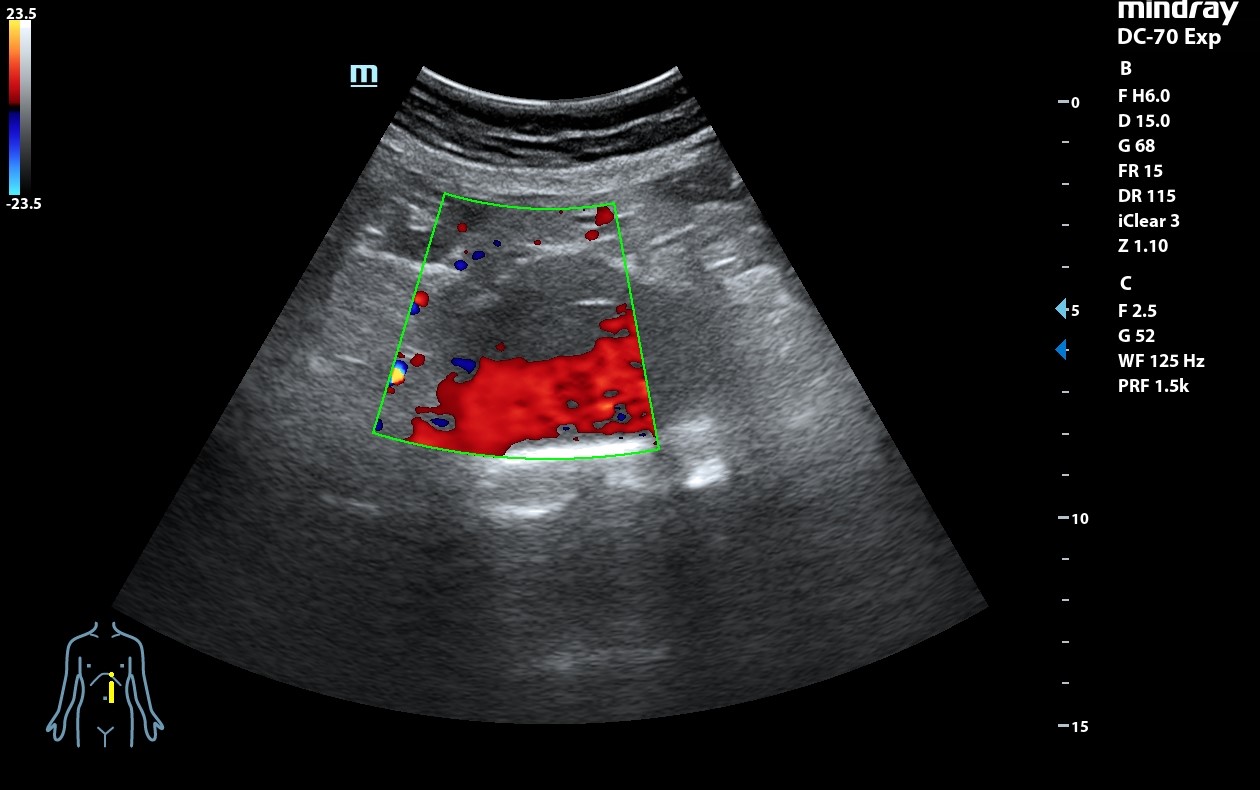

Ecografía clínica: arteria femoral dilatada con material hipoecoico heterogéneo en su pared lateral con un diámetro de 5,85 x 5,88 cm. Dilatación de aorta infrarrenal de 5,1 cm.

Nueve días después el paciente vuelve a acudir a SUH por empeoramiento del dolor en las últimas 24 horas. Se le realiza TAC de urgencias y se ingresa en CV con el diagnóstico de rotura de pseudoaneurisma arteria femoral derecha y se realiza cirugía de manera urgente.

Informe TAC aorta: Dilatación aneurismática de la aorta abdominal infrarenal, de 5 x 5 x 6,4 cm, sin signos de complicación. Imagen sacular de la arteria femoral derecha compatible con pseudoaneurima, que asocia hematoma circundante, de al menos 8,6 x 7,8 x 8,8 cm con áreas de extravasación de contraste en fase arterial, sugestivas de sangrado activo de alto débito.